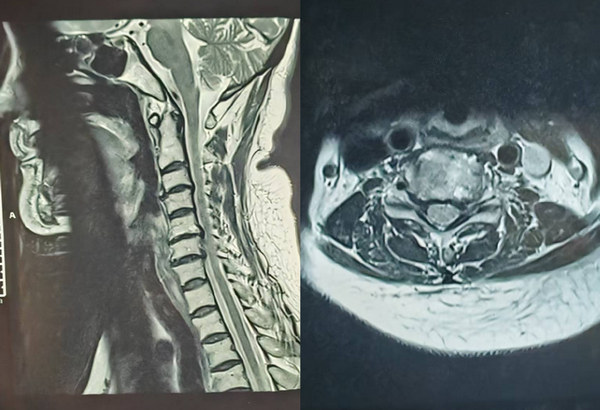

病人术前影像资料